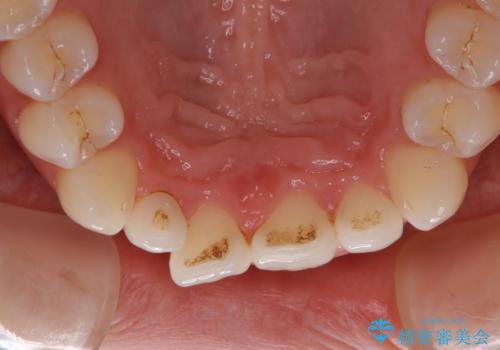

- ホワイトニングで、ご自身の歯を白くしたいと来院されました。

医院で行う、オフィスホワイトニングで歯が白くなり、喜んでいただけました。

ホワイトニングの注意事項(リスク・副作用など)

- 知覚過敏が出ることがあります

- ホワイトバンドや白い斑点が出ることがあります

- クラウンやインレー等の補綴物には効果がありません